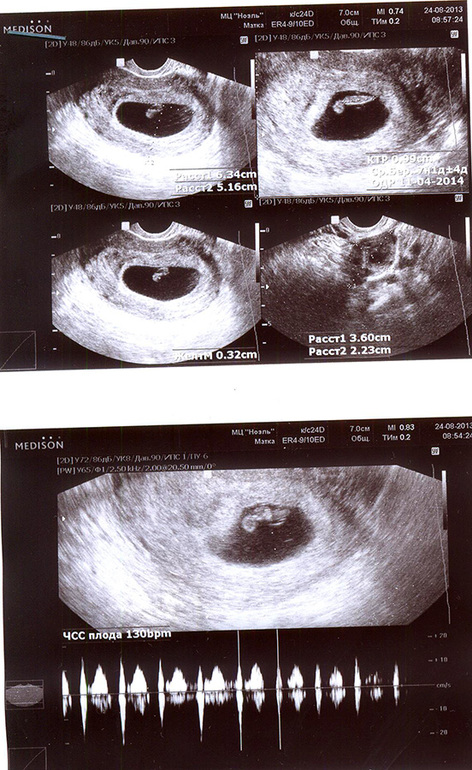

Результаты: УЗИ, КТГ, доплера, скринингаЯ только что пришла с УЗИ! Я СЛЫШАЛА СЕРДЕЧКО! 7,4 недели(это сам плод).